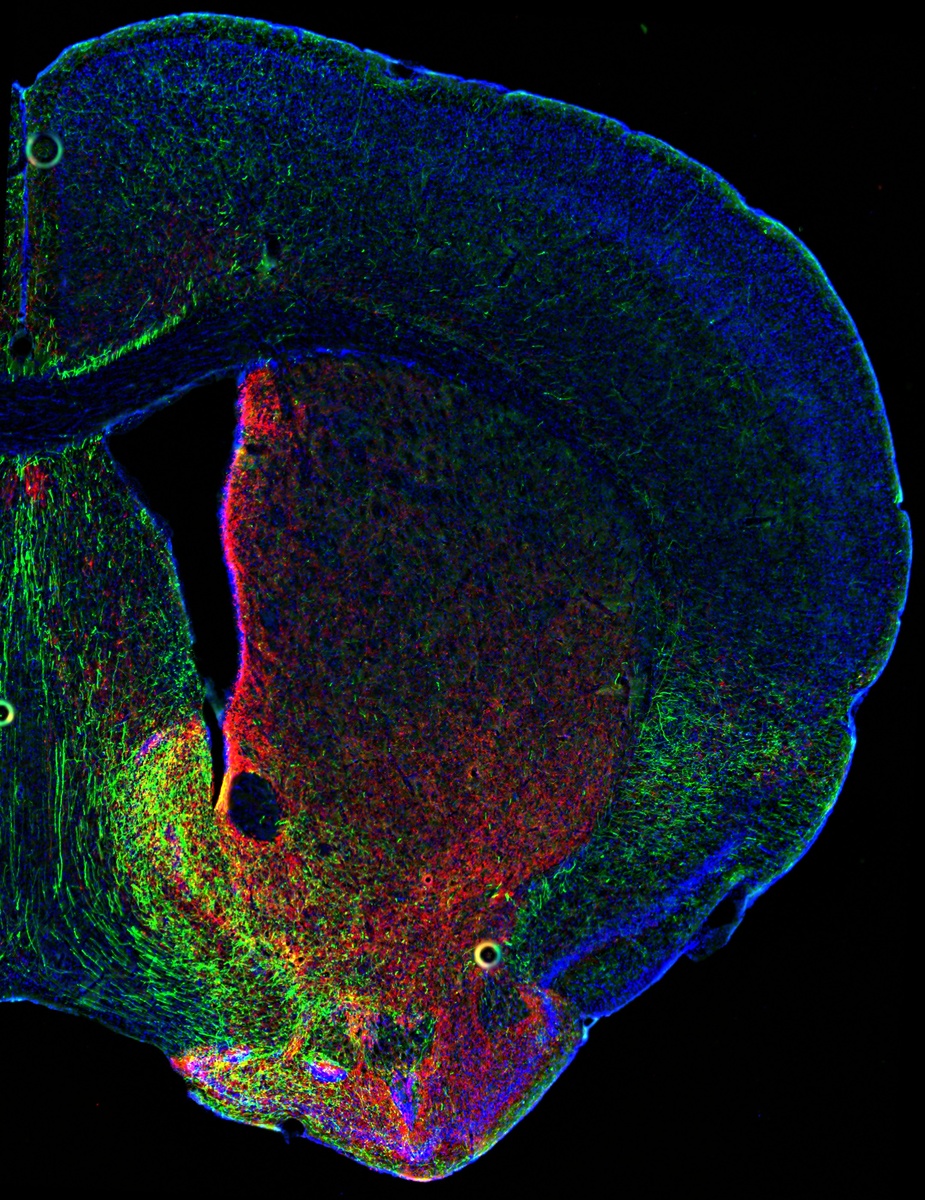

Двойная трансгенная линия мышей позволила одновременно визуализировать и контролировать дофаминовые и серотониновые нейроны у животных. На срезе корональной части мозга (фото выше) показано перекрытие дофамин- и серотонин-содержащих нервных волокон в прилежащем ядре /Daniel Cardozo Pinto, Malenka Lab, Stanford University